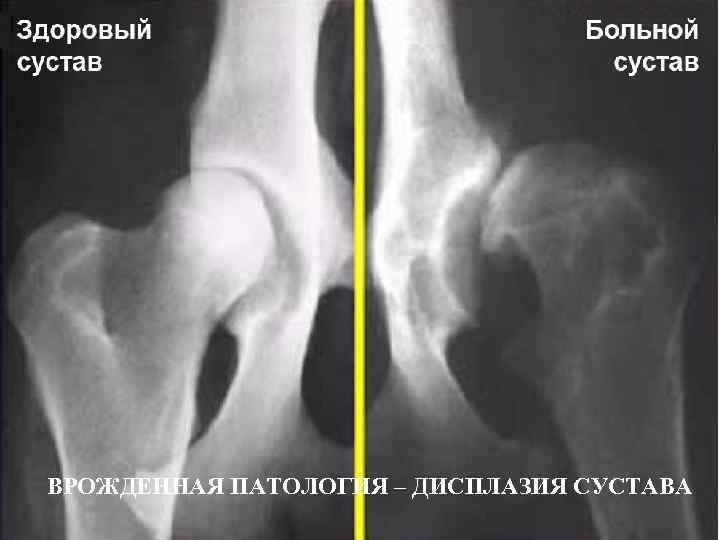

ВРОЖДЕННАЯ ПАТОЛОГИЯ – ДИСПЛАЗИЯ СУСТАВА

ПАТОЛОГИЧЕСКИЙ ВЫВИХ ПРИ ДИСПЛАЗИИ Т/Б СУСТАВОВ